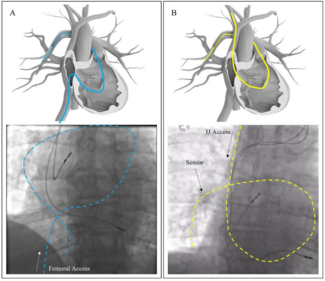

Raúl Moreno-Gómez, MD, PhD; Guillermo Galeote, MD, PhD; Borja Rivero-Santana, MD; Santiago Jimenez-Valero, MD, PhD; Silvia Valbuena, MD; Alfonso Jurado-Román, MD, PhD

This clinical image article describes a fifth left atrial appendage morphology type, which was shown to be effectively closed with current closure devices.